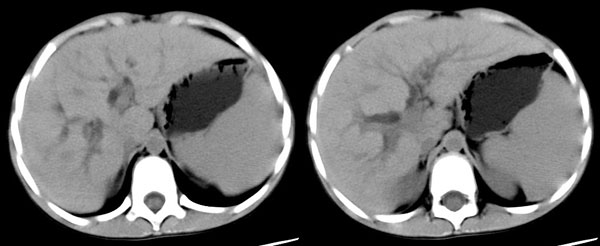

男性,9岁。体查发现肝、脾肿大。

ct平扫:肝脏稍增大,各叶比例在正常范围内,肝左叶见二个小囊肿,直径7mm-10x7mm,余肝实质未见异常密度改变。肝内胆管见轻微扩张,未见钙化结石,胆总管未见扩张。胆囊不大,壁稍增厚,内见一钙化结石达约10x6mm。胰腺形态大小密度正常。脾增大增厚,占8个肋单元,外形光整,密度均匀。双肾大小形态正常,密度均匀。腹腔内未见积液。腹膜后未见肿大淋巴结。

ct诊断:1、脾大。